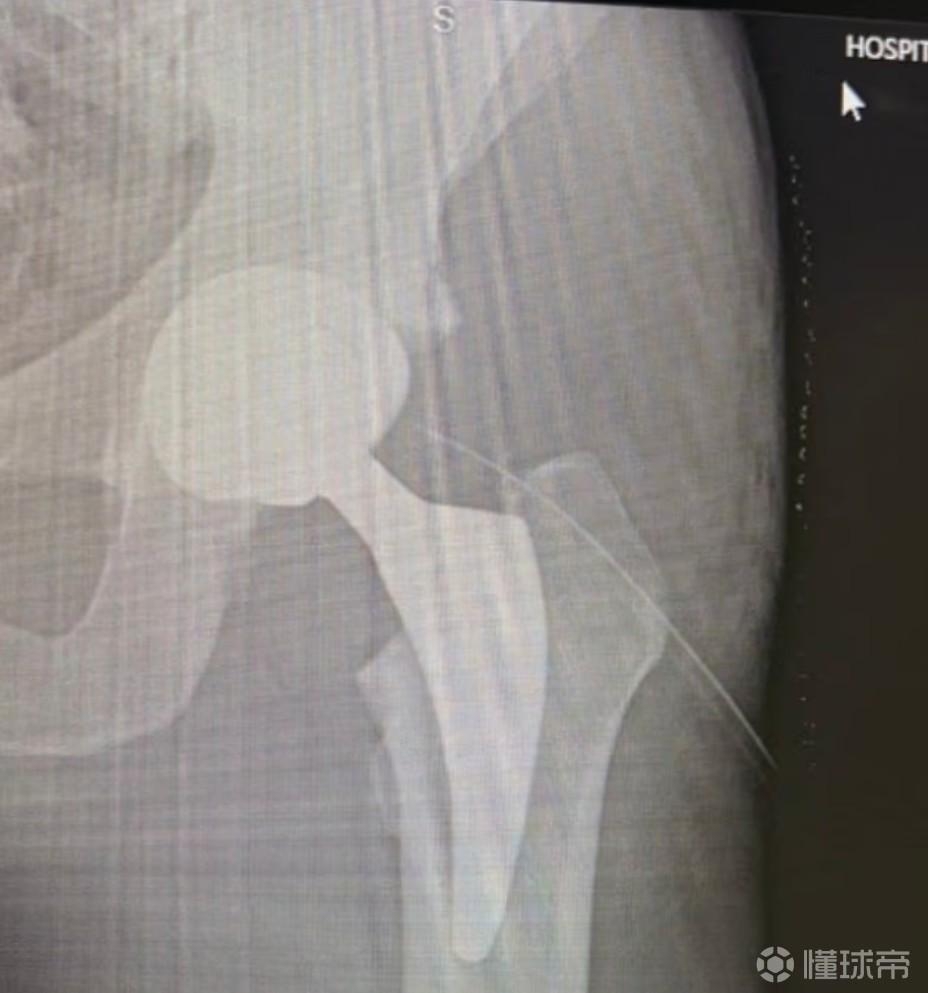

阿根廷前国脚拉梅拉在社交媒体上分享了自己做完更换人工髋关节手术后的照片。

拉梅拉写道:“有点酸痛,但有了我的新髋关节,希望这个假体将开启我无疼痛的生活。向大家问好,感谢那些一直留言的人!”

此前,拉梅拉曾在采访确认其因髋关节问题选择退役,职业生涯中,拉梅拉效力过河床、罗马、热刺、塞维利亚与雅典AEK等队。